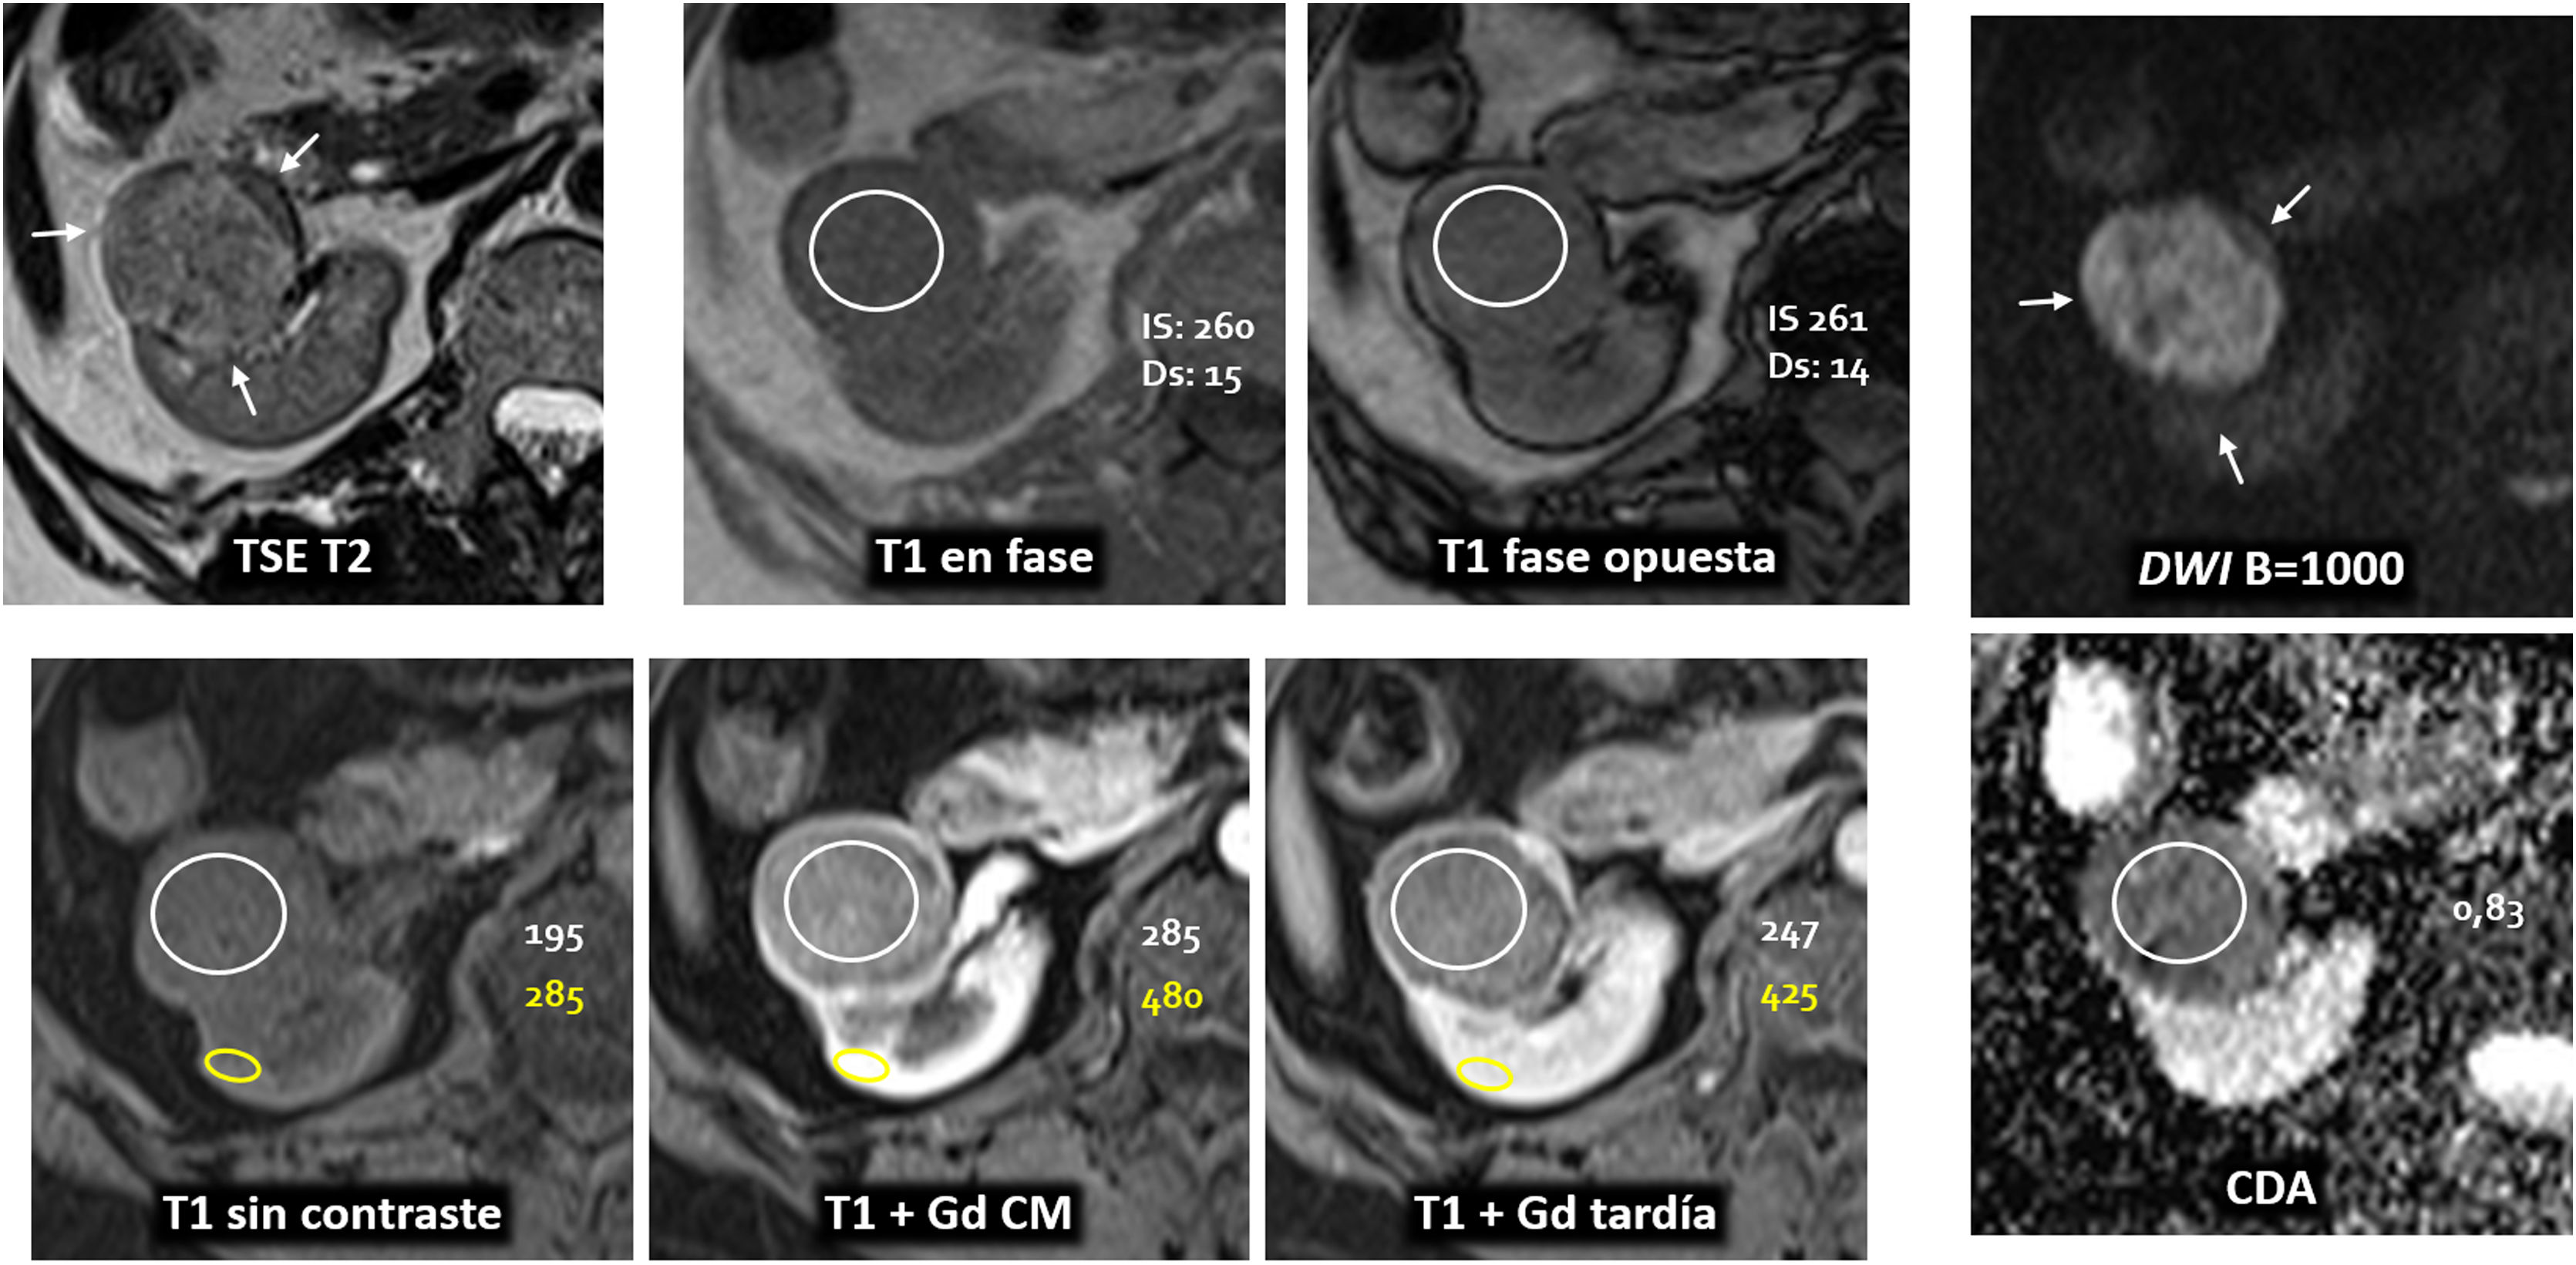

Las masas renales pequeñas incidentales plantean un reto diagnóstico, ya que un porcentaje relevante corresponde a lesiones benignas o de bajo grado, lo que ha condicionado históricamente un sobretratamiento quirúrgico. En este contexto, la resonancia magnética multiparamétrica (RMmp) y, en particular, la escala de probabilidad de carcinoma de células claras (clear cell likelihood score [ccLS]), ofrecen una aproximación estructurada y cuantitativa. El ccLS combina criterios morfológicos y funcionales en una puntuación de 1 a 5, con validación multicéntrica que respalda su utilidad en la estratificación del riesgo, especialmente en los extremos de la escala. Revisamos y describimos de forma práctica los principales aspectos de su aplicación en la interpretación sistemática de la RMmp. Por último, técnicas emergentes como radiómica, inteligencia artificial o imagen molecular ofrecen perspectivas futuras, si bien el ccLS es actualmente la herramienta más consolidada.

Incidental small renal masses (SRMs) pose a diagnostic challenge because a substantial proportion are benign or low-grade lesions, which has historically led to overtreatment with surgery. In this context, multiparametric magnetic resonance imaging (mpMRI), and particularly the clear cell likelihood score (ccLS), offers a structured and quantitative approach. The ccLS integrates morphological and functional criteria into a 5-point scale (1-5), with multicentre validation supporting its utility in risk stratification, especially at the extremes of the scale. We provide a practical review and description of the main aspects of its application in the systematic interpretation of mpMRI. Finally, emerging techniques such as radiomics, artificial intelligence and molecular imaging may gain in importance in the future but ccLS is the most established tool at present.